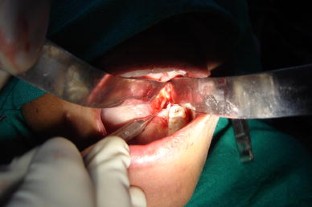

Fig. 4